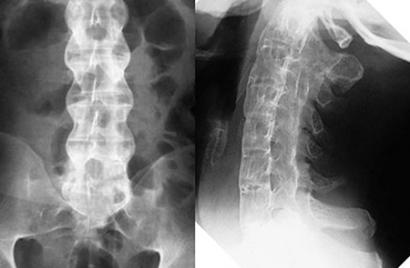

XẸP ĐỐT SỐNG CHỮA THẾ NÀO MỚI HIỆU QUẢ

XẸP CỘT SỐNG CHỮA THẾ NÀO MỚI HIỆU QUẢ